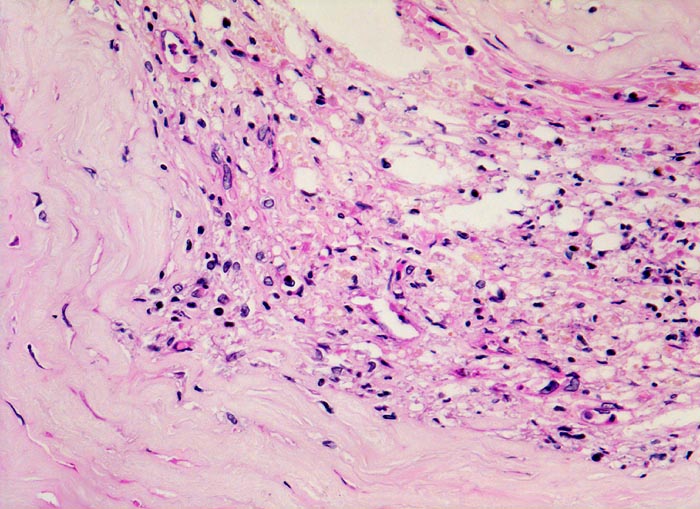

Makroskopisch sind Thromben am besten auf Querschnitten in 3 bis 5mm Abständen durch die Koronargefässe darstellbar. Thromben, die zum Tod des Patienten geführt haben, erkennt man meist makroskopisch. Mikroskopisch findet sich ein Kontinuitätsunterbruch in einer entzündlich veränderten fibrösen Deckplatte über einem Atherom. Dadurch gerät der lipidreiche Kern des Atheroms in Kontakt mit dem luminalen Blutstrom und dies führt zur Ausbildung eines Plättchen-Fibrin Thrombus und zur Einblutung in das Atherom. Meist zeigt der Thrombus Zeichen der beginnenden Organisation. Histologisch ist bei einer Ruptur die denudierte Endotheloberfläche von einem luminalen Thrombus bedeckt.

• Atherom mit fibröser Deckplatte.

• Exzentrische Lumeneinengung durch Verdickung der Intima.

• Organisierender geschichteter Abscheidungsthrombus über Defekt in der fibrösen Deckplatte. Der Thrombus enthält zusätzlich Atherombestandteile (Cholesterinkristalle und nekrotischer Detritus).